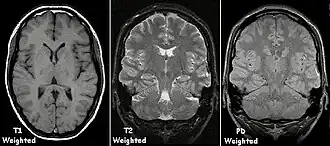

| Spin echo | T1 weighted | T1 | Measuring spin–lattice relaxation by using a short repetition time (TR) and echo time (TE). |

Standard foundation and comparison for other sequences |

| T2 weighted | T2 | Measuring spin–spin relaxation by using long TR and TE times |

| Proton density weighted | PD | Long TR (to reduce T1) and short TE (to minimize T2).[7] | Joint disease and injury.[8]

T1 and T2

Each tissue returns to its equilibrium state after excitation by the independent relaxation processes of T1 (spin-lattice; that is, magnetization in the same direction as the static magnetic field) and T2 (spin-spin; transverse to the static magnetic field). To create a T1-weighted image, magnetization is allowed to recover before measuring the MR signal by changing the repetition time (TR). This image weighting is useful for assessing the cerebral cortex, identifying fatty tissue, characterizing focal liver lesions, and in general, obtaining morphological information, as well as for post-contrast imaging. To create a T2-weighted image, magnetization is allowed to decay before measuring the MR signal by changing the echo time (TE). This image weighting is useful for detecting edema and inflammation, revealing white matter lesions, and assessing zonal anatomy in the prostate and uterus.

Proton density

Proton density (PD)- weighted images are created by having a long repetition time (TR) and a short echo time (TE).[36] On images of the brain, this sequence has a more pronounced distinction between grey matter (bright) and white matter (darker grey), but with little contrast between brain and CSF.[36] It is very useful for the detection of arthropathy and injury.[37]